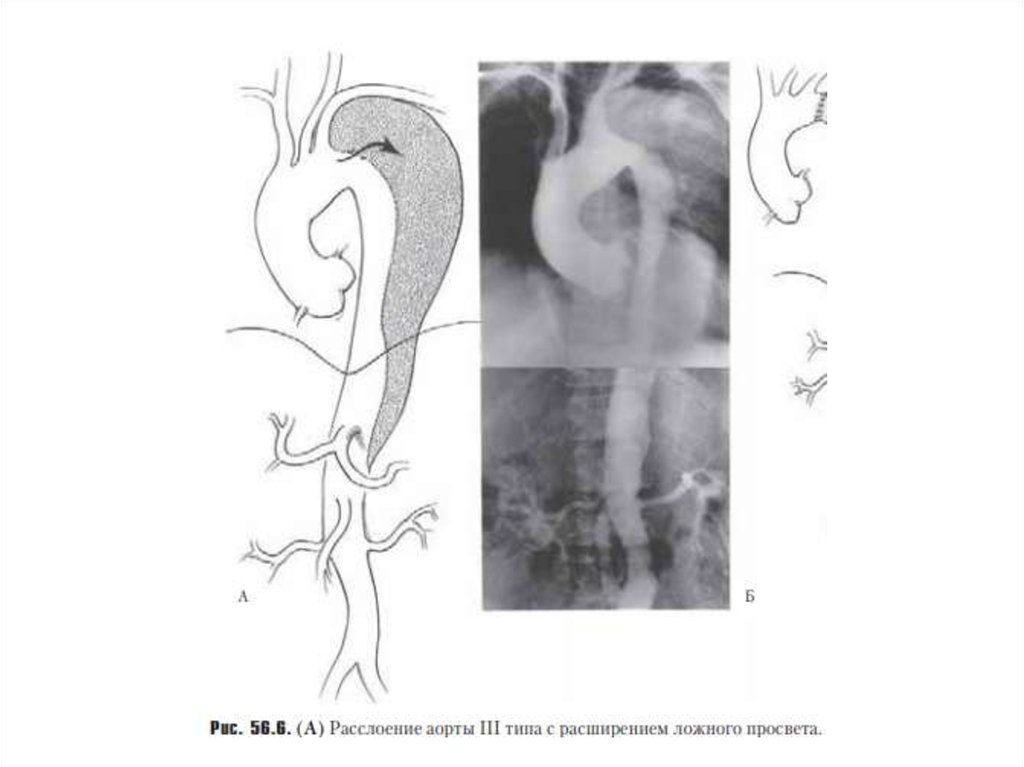

Тип 3 – разрыв интимы локализуется в нисходящей грудной аорте, распространяется чаще антеградно

дистально, по нисходящей аорте на различном протяжении с вовлечением только всего грудного

отдела и/или и грудного и брюшного отделов, редко –ретроградно на дугу и восходящую часть аорты

Классификация по De Backey